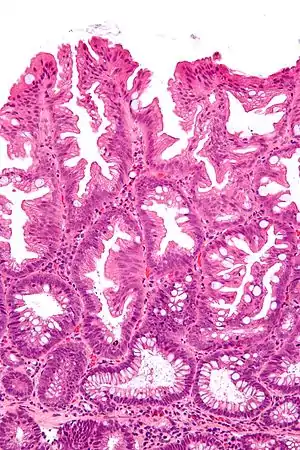

Tubulovillous adenoma

Tubulovillous adenoma, TVA are considered to have a higher risk of becoming malignant (cancerous) than tubular adenomas.[9]